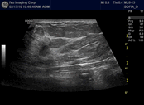

Tomographic Whole Breast images

2D / 3D and MPR Analysis Tools